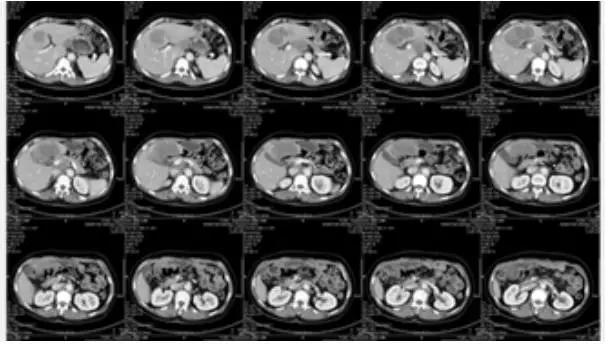

图5 2016年1月5日CT

患者于2015年11月开始出现大量蛋白尿(3-5g/24h),因此将阿帕替尼减量至425mg qd口服,但蛋白尿未见明显减少,遂停药2周(2015年12月17日至2016年1月5日),停药后蛋白尿降至0.72g/24h。2016年1月5日CT提示肝实质内大片状低密度病灶,较前增大110%。肠系膜区、腹膜后多发淋巴结,部分较前明显增大。AFP由7700升高至42000ng/ml。因此本次疗效评估为PD,二线阿帕替尼单药的TTP达到了9个月。